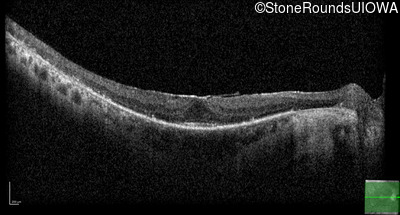

Optical Coherence Tomography - Right - 20/20

Exemplar / OCT Stack

OCT Stack